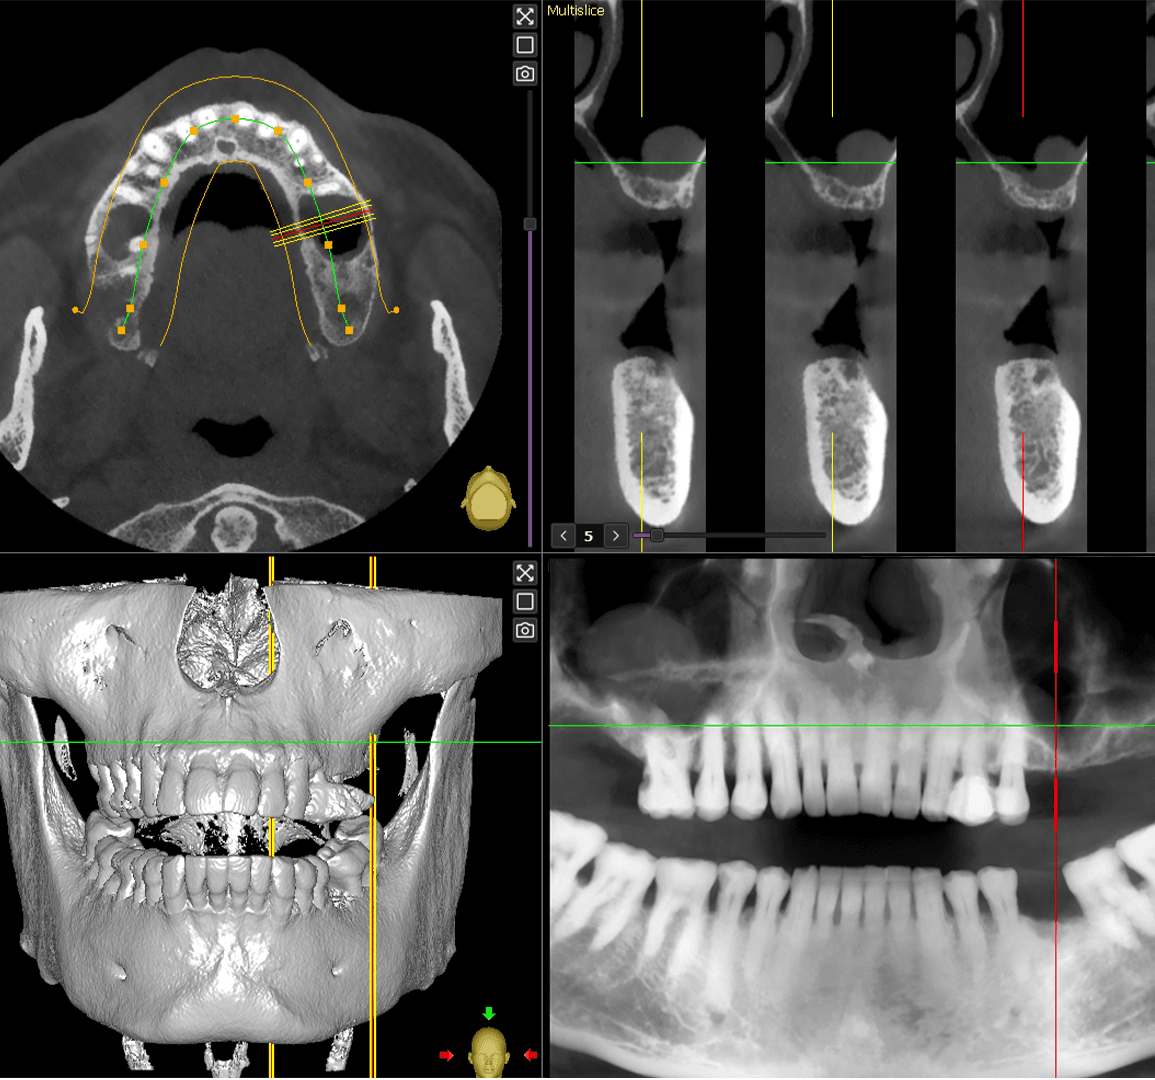

Implant Planning

We will utilize your CBCT scan and diagnostic models/.STL files to develop a preliminary treatment plan. Following this, you will have the option to determine the final implant placement.